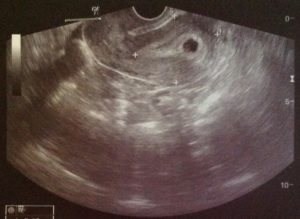

УЗИ на таком раннем сроке проводится, если для этого есть медицинские показания. В этот период плод активно растет, поэтому при помощи исследования можно определить наличие беременности, а также возможные аномалии.

Актуально проведение УЗИ на четвертой неделе для определения возможных патологий репродуктивных органов пациентки. Своевременно выявленные аномалии позволяют определить необходимое лечение в будущем. Исследование проводится, чтобы своевременно выявить признаки внематочной беременности.